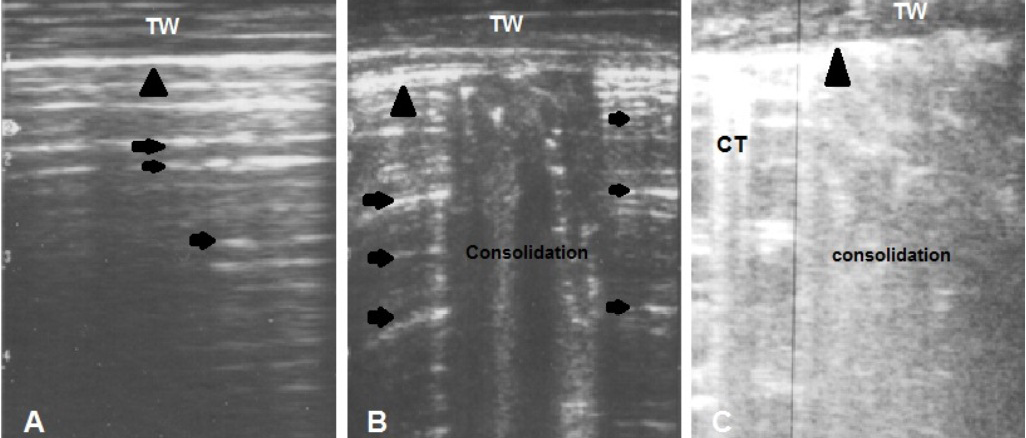

Figure 2

(A) Ultrasonogram of normal lung shows presence of reverberation artifact (arrows) medial to the hyperechoic pleura (arrow head)

(B) Focal area of consolidation in between normal lung tissue (mild cases)

(C) Diffuse area of consolidation and comet tail (CT) artifact reflect presence of severe disease. TW: Thoracic wall